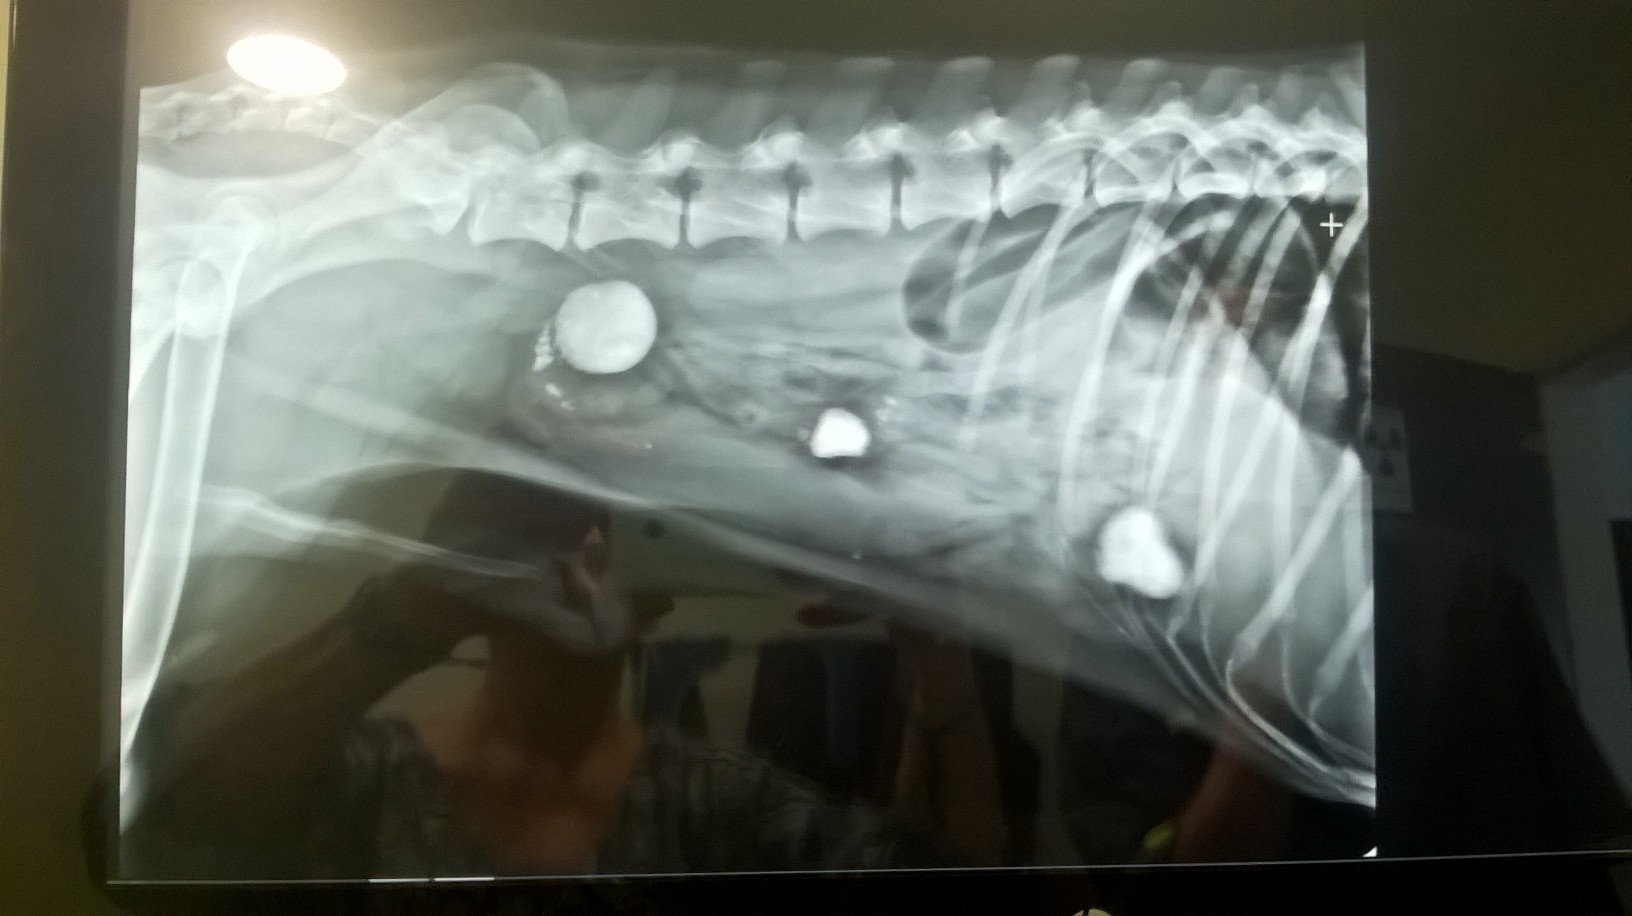

hier soir véto, radio, rien de détecté, pas d'occlusion "pour l'instant", traitement à base de pansement gastrique et laxatif (au cas où il y aurait des morceau de plastique à évacuer).